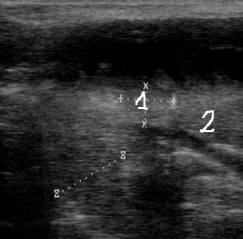

При остром послеродовом эндометрите мы наблюдали

незначительное повышение температуры тела, обильное выделение бурого экссудата

с прожилками гноя; при ректальном исследовании матка располагалась позади

лонного сращения, дрябловатая на ощупь. Ультразвуковая картина характеризуется

наличием в полости матки относительно однородного гипоэхогенного содержимого от

значительного до небольшого объема. Слизистая оболочка утолщена и разрыхлена,

хорошо визуализируются карункулы, что связано с нарушением инволюционных

процессов половых органов (рис. 2).

Рис. 2. Ультразвуковая картина

при остром эндометрите.

Цифрами обозначены: 1 –

карункул; 2 – полость матки с жидкостью.